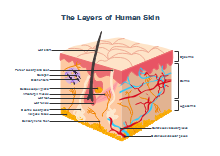

illustrazione scientifica - anatomia umana